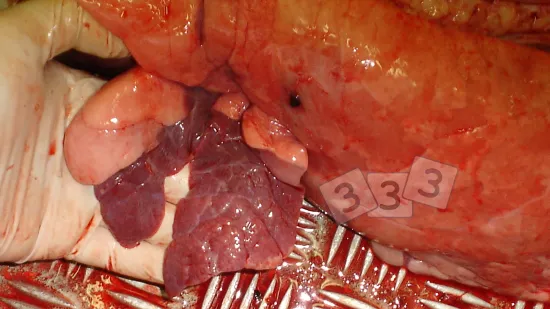

Semaine du 02-Jan-2024

Il y a une épidémie de morts subites, perte d'appétit, forte fièvre et respiration laborieuse chez des porcs de 15 semaines jusqu'à l'abattage. L'inspection à l'abattoir montre des poumons comme ceux de la photo. Quelle est la cause la plus probable?